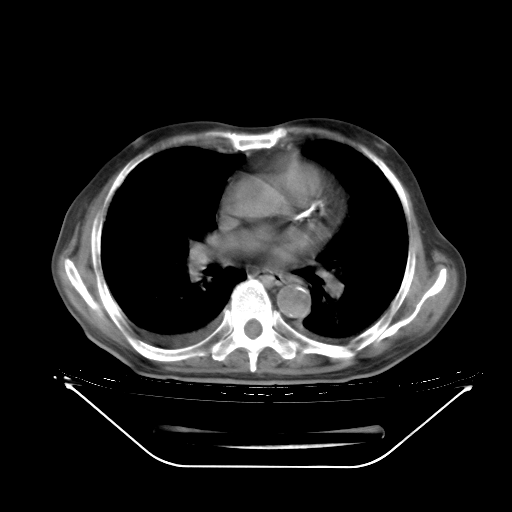

今天复查肺部CT,发现双肺广泛磨玻璃样改变。所以我把3月19日和5月9日相隔50天的肺部CT上传。请大家会诊。

2009年3月19日肺部CT片。

2009年3月19日肺部CT